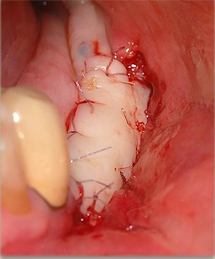

• Tecniche di aumento tessuti molli perimplantari

• Il prelievo connettivale: tecnica step-by step

• Gestione dei tessuti molli nella gbr